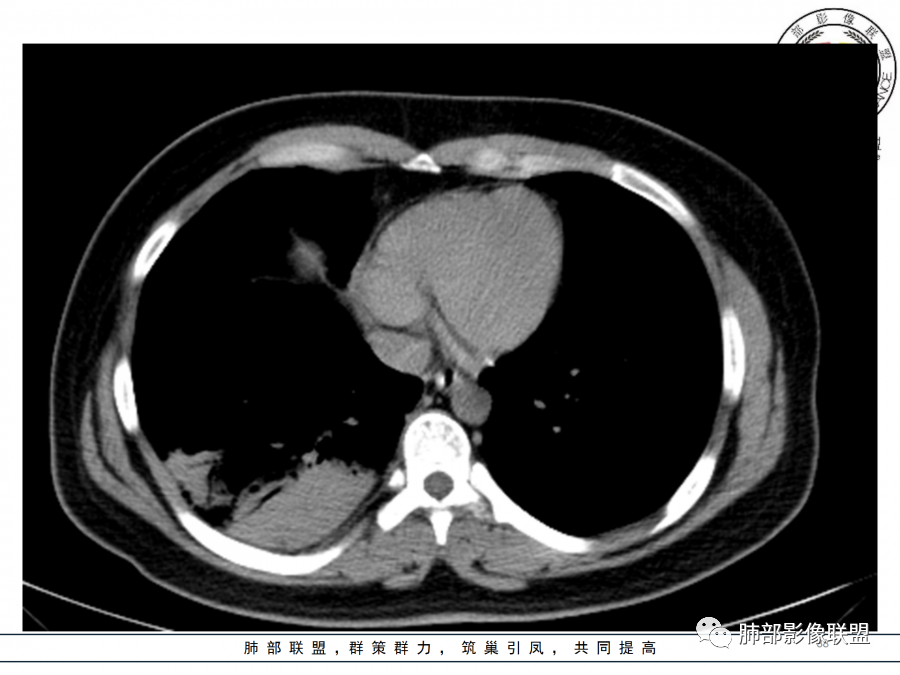

1.年轻女性,咳嗽、发热(38.8°),起病急,血象高。影像上大片实变影为主,一般会首先考虑细菌性肺炎,尤其是肺炎链球菌感染等。疗效不满意时考虑其他。

2.影像上怀疑其他病灶的理由有:

1)实变影为大小不等多中心性。

2)沿胸膜下分布趋势(不同于大叶性肺炎的肺叶“造型”)。

3)周围较大范围磨玻璃影及小叶间隔增厚。

4)病灶体积增大明显(叶间裂推移)。

3.腺病毒肺炎可以符合上述改变:实性密度,间质分布为主等。

4.隐球菌感染可以符合上述改变:胸膜下多中心实变密度为主,磨玻璃晕等。但隐球菌临床症状大多隐匿、迁延,影像变化缓慢。

5.本例患者血象高,影像渗出明显,尚不能排除混合感染可能。